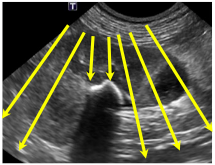

Quel est cet artéfact?

=> RÉVERBATION

distal à du gaz : se présente comme pleins de lignes parallèles distalement à la structure gazeuse